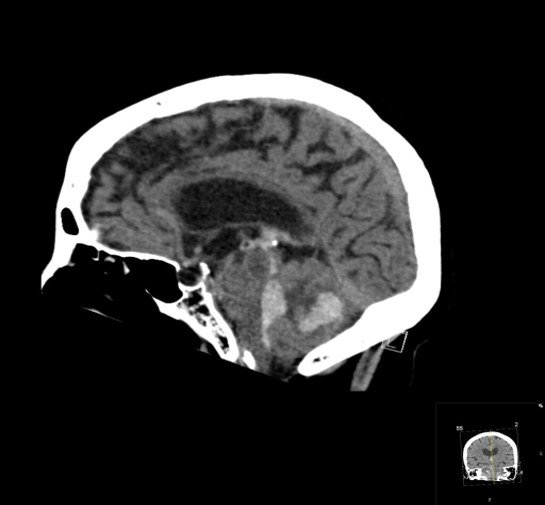

CASE 2 -A 54-year-old man walks into emergency 3 hours after a 150kg plank of wood fell on his head. He has obvious external signs of head injury and a cracking headache, however, neurologically he is intact. A CT head scan is performed

EXPLANATION –There is a depressed right parietal bone fracture with underlying pneumocephalus (indicates an open skull fracture) and a small subdural hematoma.

- Overlying this there is a scalp hematoma.

- There is also a non-displaced fracture in the frontal bone. This fracture crosses the midline and probably has injured the anterior aspect of the superior sagittal sinus.

- Tears of the dural venous sinuses may cause an extradural hematoma (EDH), as in this case. The hematoma is seen external to the compressed superior sagittal sinus.

Extradural bleeds (EDH) are located between the outer layer of dura and endosteal layer of skull. Like in this case, they are usually associated with calvarial fractures.

- They typically demonstrate biconvex or lentiform shape and are limited by sutures as periosteum is attached at the sutures limiting spread of the bleed.

- The source of bleed is arterial in origin, from a middle meningeal artery as opposed to venous in subdural bleeds.

- Up to 10% of EDH are due to venous bleeding, follow the laceration of a dural venous sinus, as we see in this case.

- There is often displacement of the sinus away from the underlying bone. There are three locations characteristic of venous EDH; the vertex, anterior middle cranial fossa and the occipital posterior fossa.

- Hypodense areas within a bleed likely represent unclotted blood suggesting active bleeding.

- As these bleeds are venous, there is not the same urgency for decompression in theatre. In fact, this patient was managed conservatively as operative intervention poses a risk of further damage to the venous sinuses.